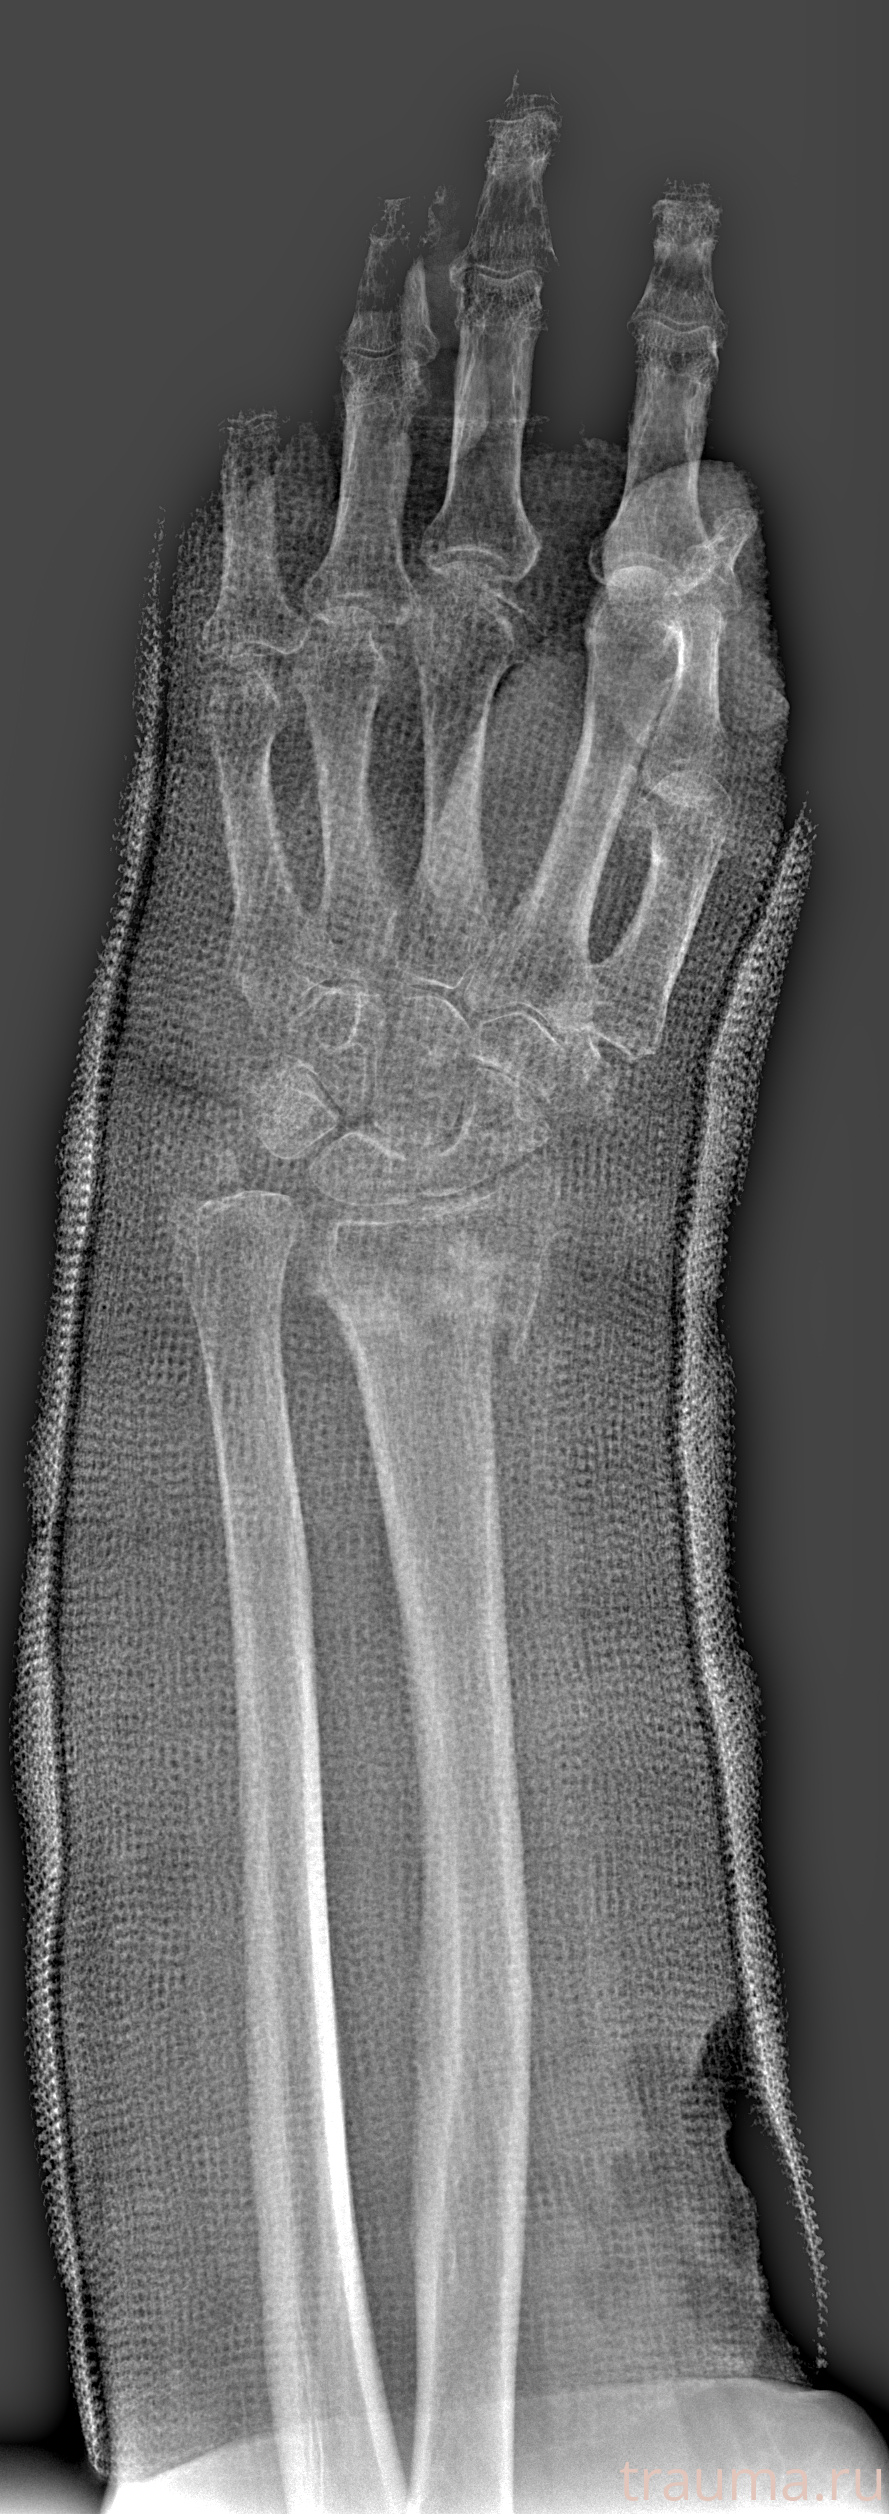

Рентген на дому: по вашему адресу приезжает врач-рентгенолог, травматолог-ортопед с мобильным рентгеновским аппаратом, проводит диагностику травмы или заболевания, делает необходимые рентгенограммы, дает рекомендации по дальнейшему лечению. Получить качественные снимки в домашних условиях возможно благодаря уникальной методике, разработанной МосРентген Центром для института  Склифосовского